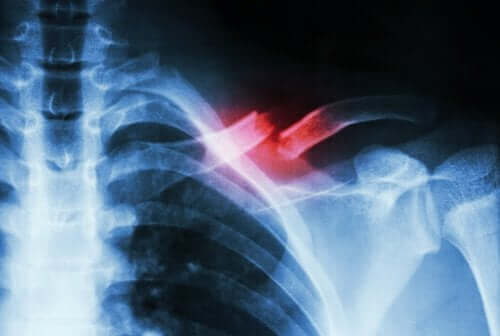

En stressfraktur forekommer, når der er et lille brud på en knogle, der har oprindelse i noget andet end et kraftigt slag. Typisk er det enten udløst af gentagende bevægelser eller af en hurtig stigning i mængden eller intensiteten af en aktivitet.

En stressfraktur er en slags spalte eller en revne i knoglen. Det sker på grund af gentagende mikrotrauma eller overbelastning, som vi nævnte ovenfor. Derudover kan de udgøre svær smerte, når visse fysiske aktiviteter udføres. Derefter forsvinder de ofte, når aktiviteterne slutter.